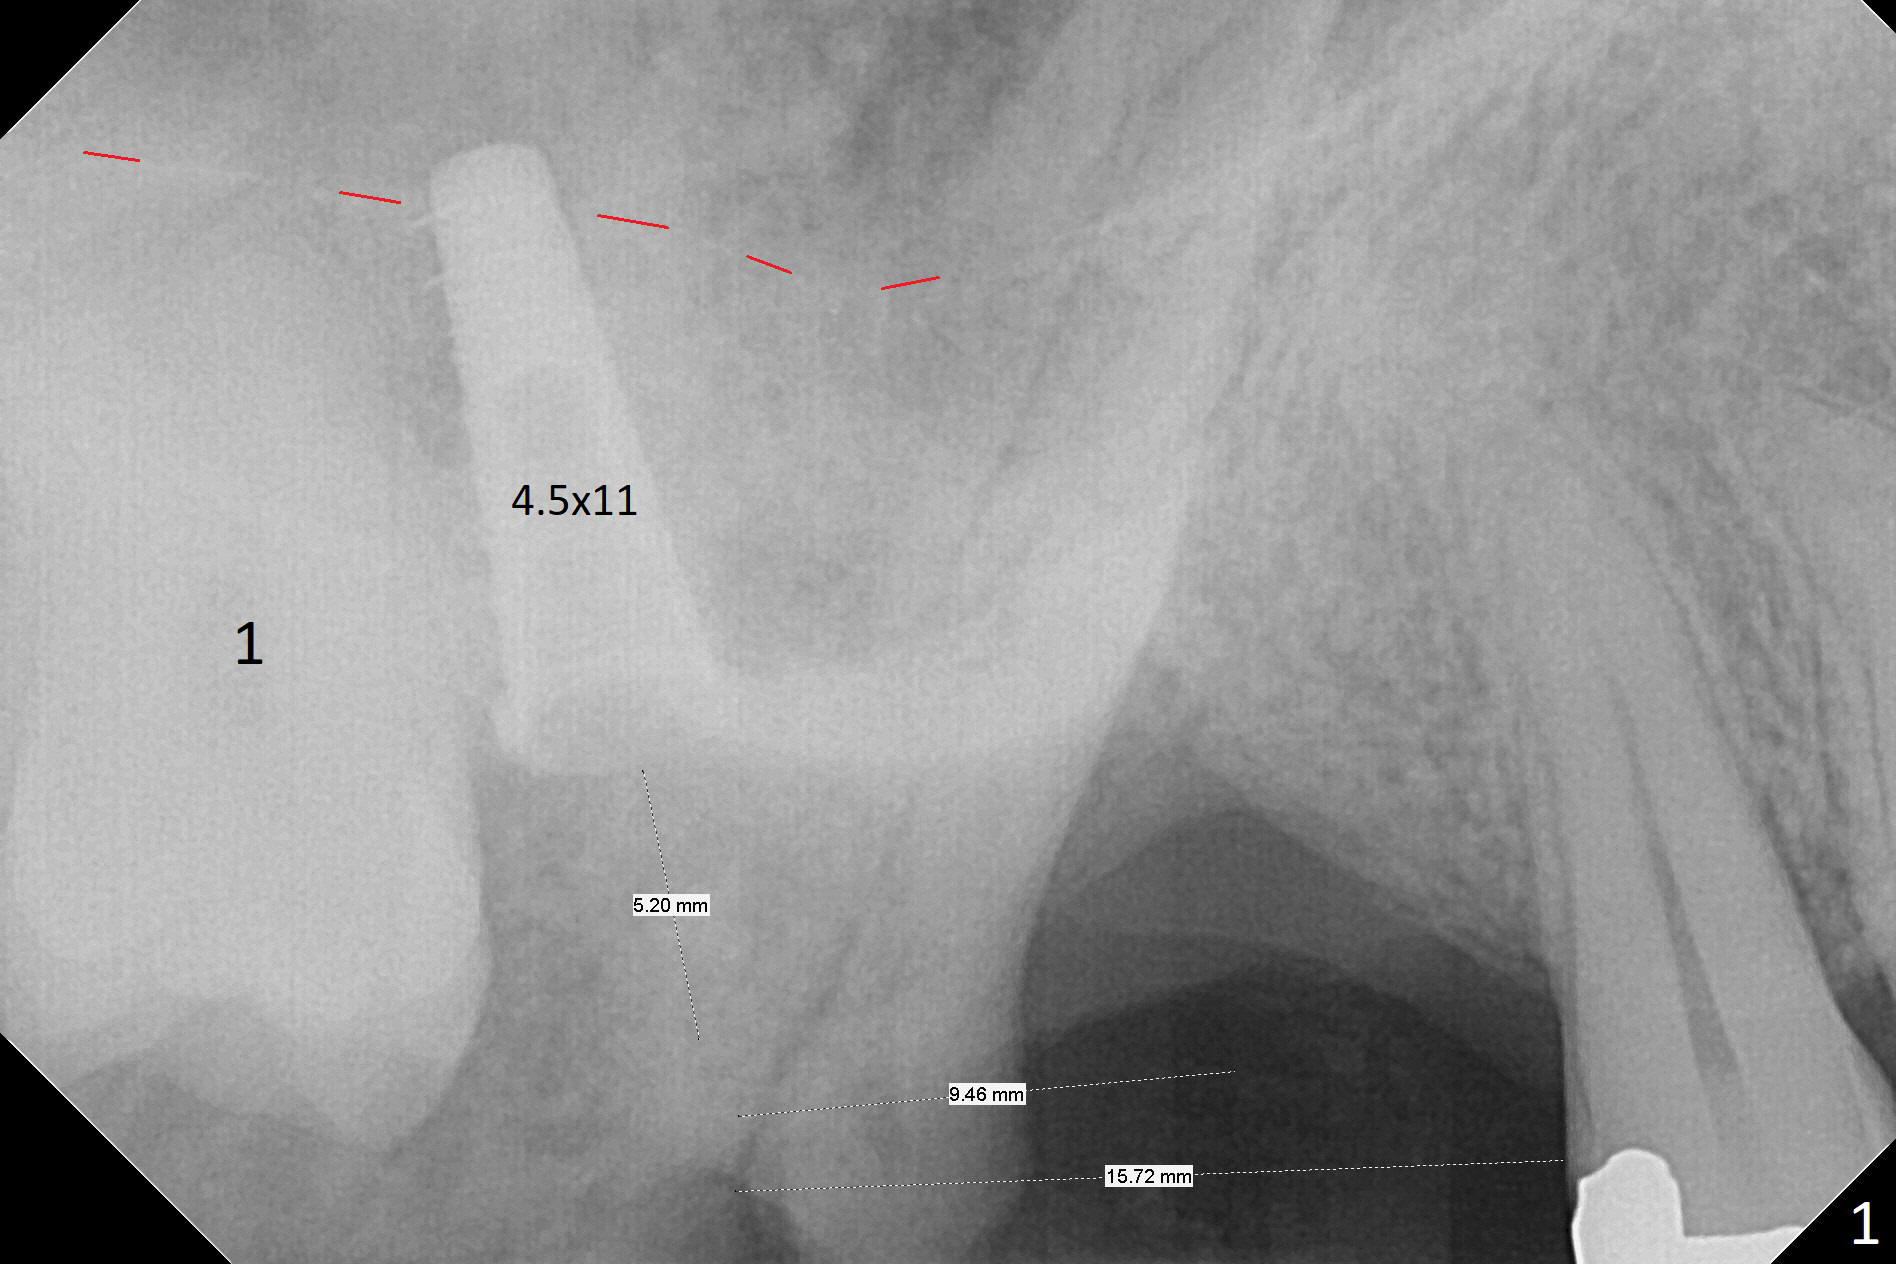

It is difficult to use hard tissue landmark (drill stopper) to make osteotomy in the fresh extraction socket because of socket irregularity and hemorrhage. Once osteotomy is initiated, depth is more reliably controlled with soft tissue landmark (such as gingival margin). This happens in today's case. Without CT information, the osteotomy is established in the buccal slope of the septum of the tooth #2 (after extraction) by using alternatively Magic Sinus Lifter and 4.8 mm Magic Drill (MD). Finally the sinus floor (Fig.1 red dashed line) is lifted after the MD reaches ~16 mm counting from the gingival margin, consistent with preop panoramic X-ray and intraop PA measurement. The 4.5x11 mm dummy implant is close to the impacted 3rd molar (1). Following use of Lindamann bur to move the osteotomy mesially, a 5x9 mm dummy implant is placed away from the 3rd molar (Fig.2 (3: residual root of the 1st molar)). The latter is intentionally not removed in order to maintain osteotomy integrity. A 5x13 mm IBS implant is placed with >50 Ncm; a 6.5x4(4) mm abutment is hand tightened (Fig.3). The remaining large socket is filled with Vera Graft (Fig.4 *). Two months postop, the abutment changes to 6.5x5.7(2) mm without provisional (Fig.5). Nearly 3 months postop, the patient will return for #3 residual root extraction and implant placement with incision (Fig.6). Osteotomy will be initiated in a slope. Prepare surgical round bur for flattening. After placement of a healing abutment, periodontal dressing is to be applied. Take photos to show gingival adaptation to the new abutment without implant exposure at #2.